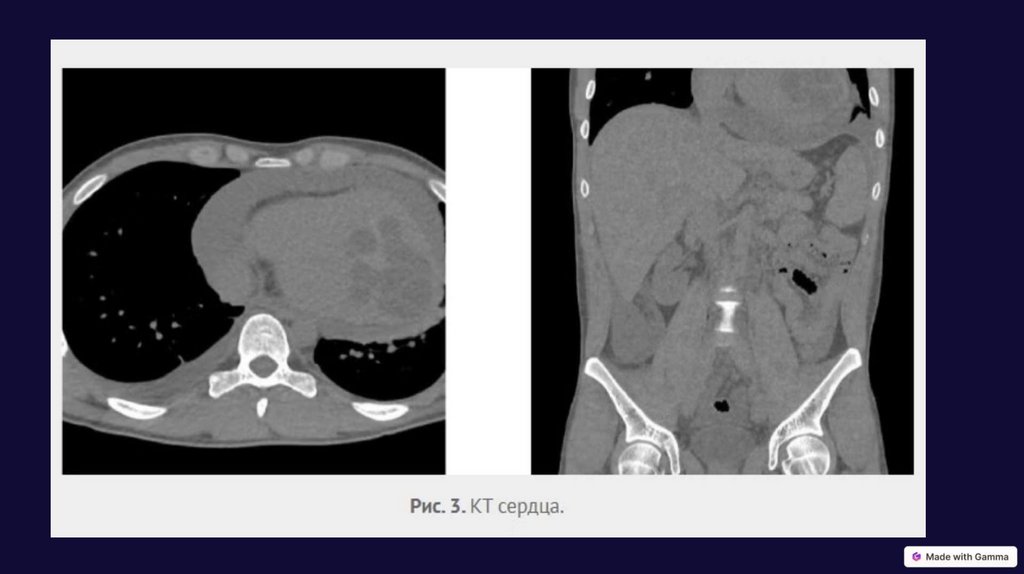

Эхинококкоз сердца